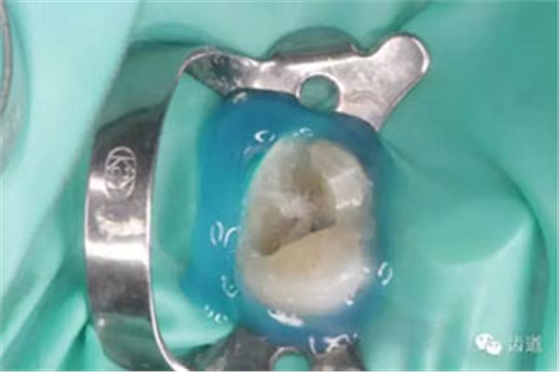

處理:顯微根管治療。放置橡皮障,去除暫封,顯微鏡下超聲去除頰側(cè)根管上段部分牙本質(zhì),探及遠(yuǎn)中根管口,見(jiàn)有糊劑遮蓋。Pathfile根管疏通,MTwo根管預(yù)備至2506#,配合3%次氯酸鈉和17%EDTA超聲蕩洗,干燥根管,放置氫氧化鈣糊劑,zoe暫封。

處理:放置橡皮障,去除暫封,超聲結(jié)合2%CHX清除遠(yuǎn)頰根管內(nèi)氫氧化鈣糊劑,主牙膠試合后95%酒精沖洗干燥根管,結(jié)合AHPlus糊劑連續(xù)波熱牙膠垂直加壓充填根管,樹(shù)脂分層粘接修復(fù)牙體。建議定時(shí)復(fù)診進(jìn)行嵌體修復(fù),患者未執(zhí)行。